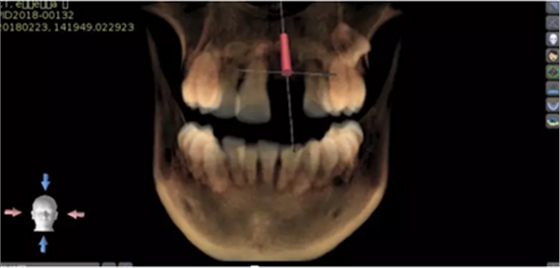

2.術(shù)前植體設(shè)計(jì)

3.術(shù)前導(dǎo)板設(shè)計(jì)

21牙種植手術(shù)

頜面部消毒→鋪襟→局麻下翻瓣→帶入導(dǎo)板→定位鉆定位→擴(kuò)孔鉆擴(kuò)孔→植入3.0x13植體→覆蓋螺絲→縫合→沖洗→術(shù)后醫(yī)囑